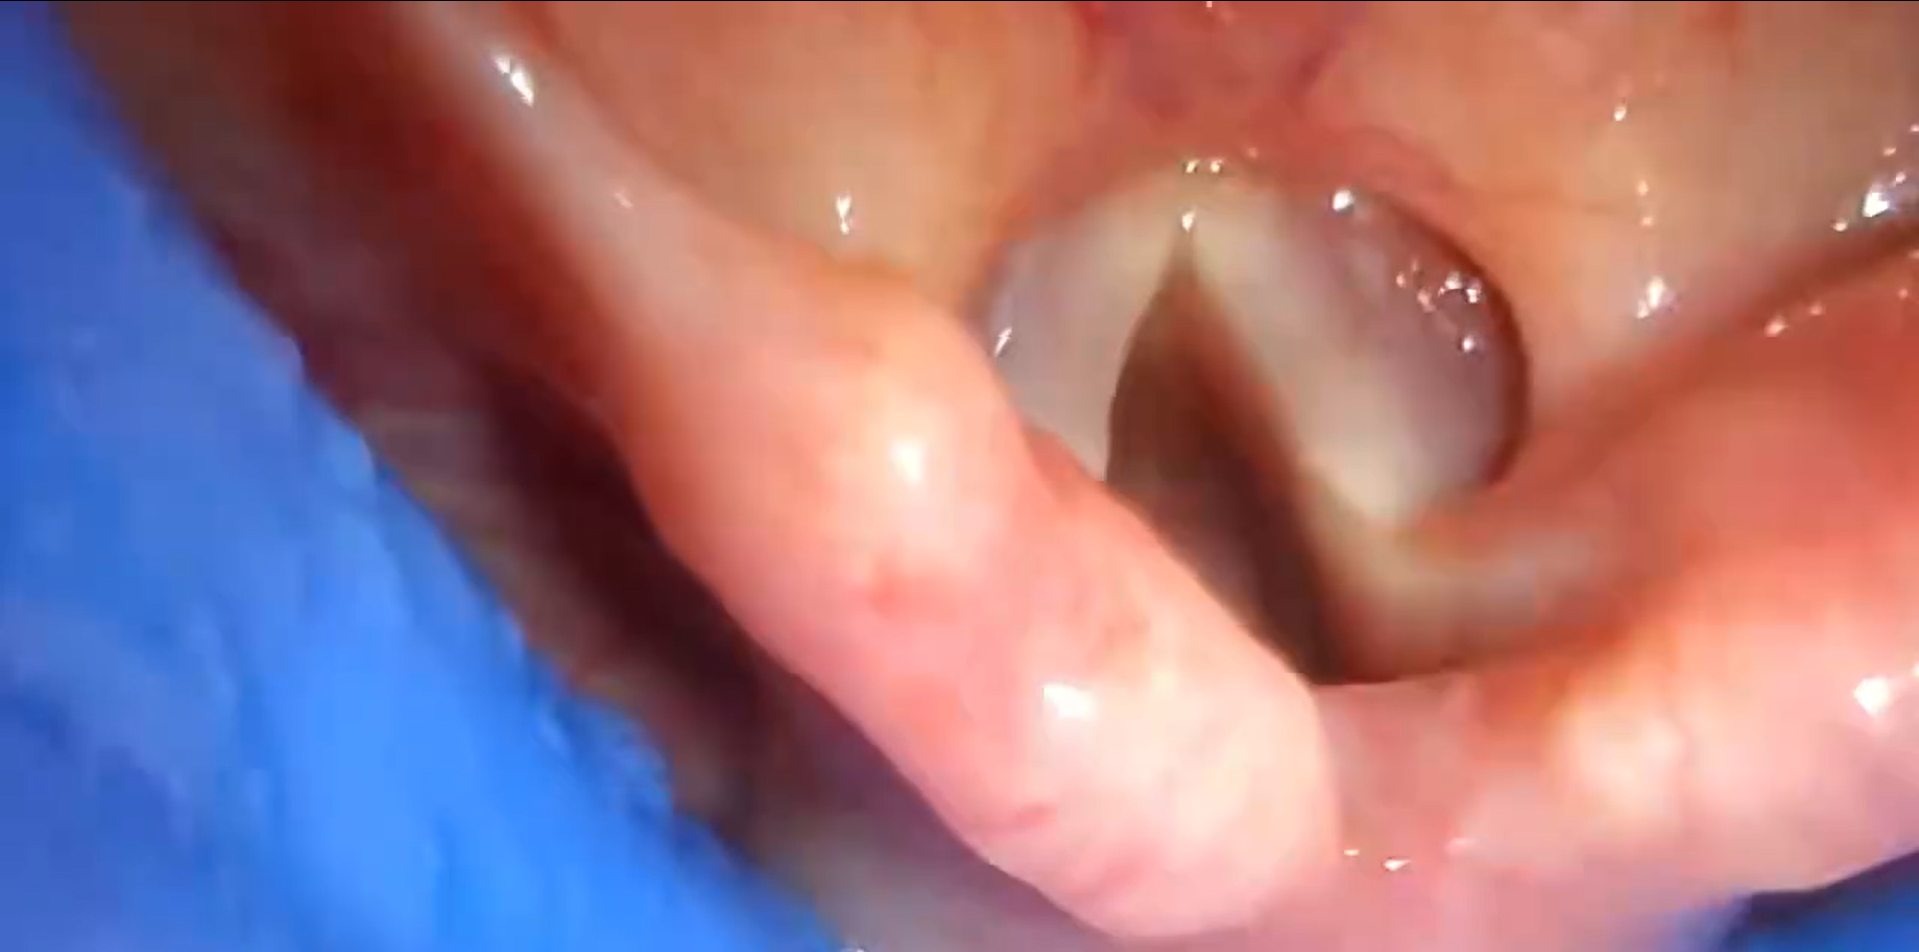

Visualize the key anatomical landmarks to orient yourself during mask insertion and placement.

Ensure a full and even deflation of the cuff to ensure the folds to not block the camera view. Apply a water based lubricant to the posterior aspect of the cuff, away from the camera.